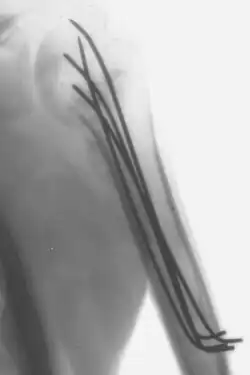

Fios de Kirschner

Os fios de Kirschner ou K-fios ou apenas pinos, são fios esterilizados, afiados, feitos de aço inoxidável liso. Foram inventados em 1909 pelo médico e cirurgião alemão Martin Kirschner, os fios são hoje amplamente utilizados em cirurgias ortopédicas e outros tipos de cirurgia médica e veterinária.

São fabricados em diferentes tamanhos e são usados para manter fragmentos ósseos juntos (fixação com pino) ou para fornecer um ponto de ancoragem para tração esquelética. Os pinos são muitas vezes inseridos no osso através da pele (fixação percutânea) utilizando um perfurador elétrico ou manual.